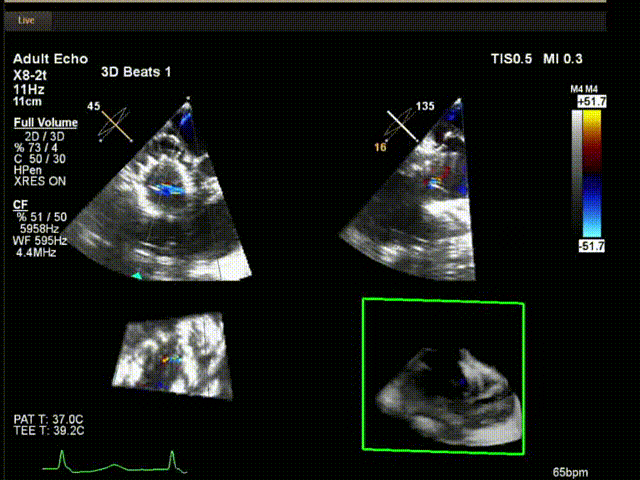

術(shù)中超聲